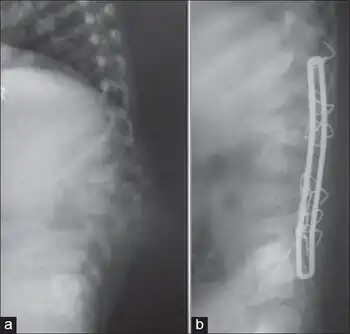

Kyphosis progression prevention

.jpg)

Surgical intervention is used in patients with kyphosis to primarily prevent the progression of kyphosis in active disease and correct it to a certain extent.[29]

However, surgical intervention is not meant to cure kyphosis in the patient and has variable rates of success in eradicating it in a patient.[29]

In the event that a patient shows signs of kyphosis, the earlier surgical intervention is given, the better the outcome for the patient.[29]